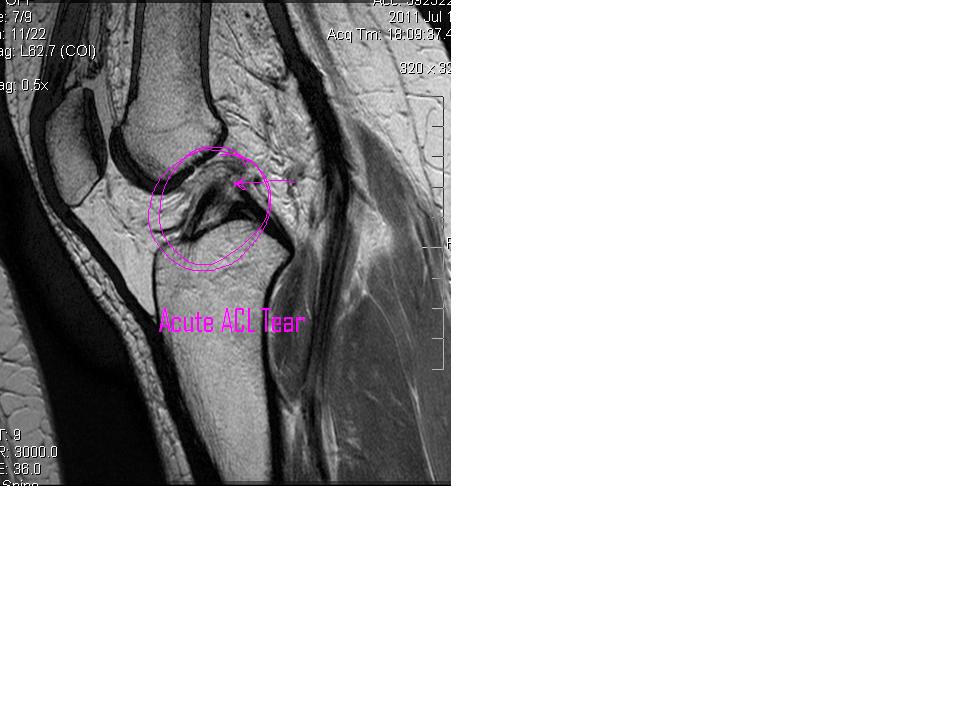

I circled the area that was of great concern to both me and Dr. Kim. It shows the ACL (thanks to my Google Medical Degree I can use that term with confidence now) torn from the femur.

Normally we should see a black band (the tendon) going from the front of the tibia (you can see that) all the way up and attaching to the back of the femur bone. The impression results from the report calls this an Acute ACL Tear.